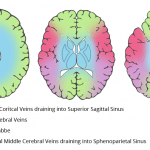

- Abnormal hyperdensity in the internal cerebral veins, the vein of Galen, and likely in portions of the thalamostriate veins

- Deep vein thrombosis with intraventricular and right caudothalamic region intraparenchymal hemorrhage